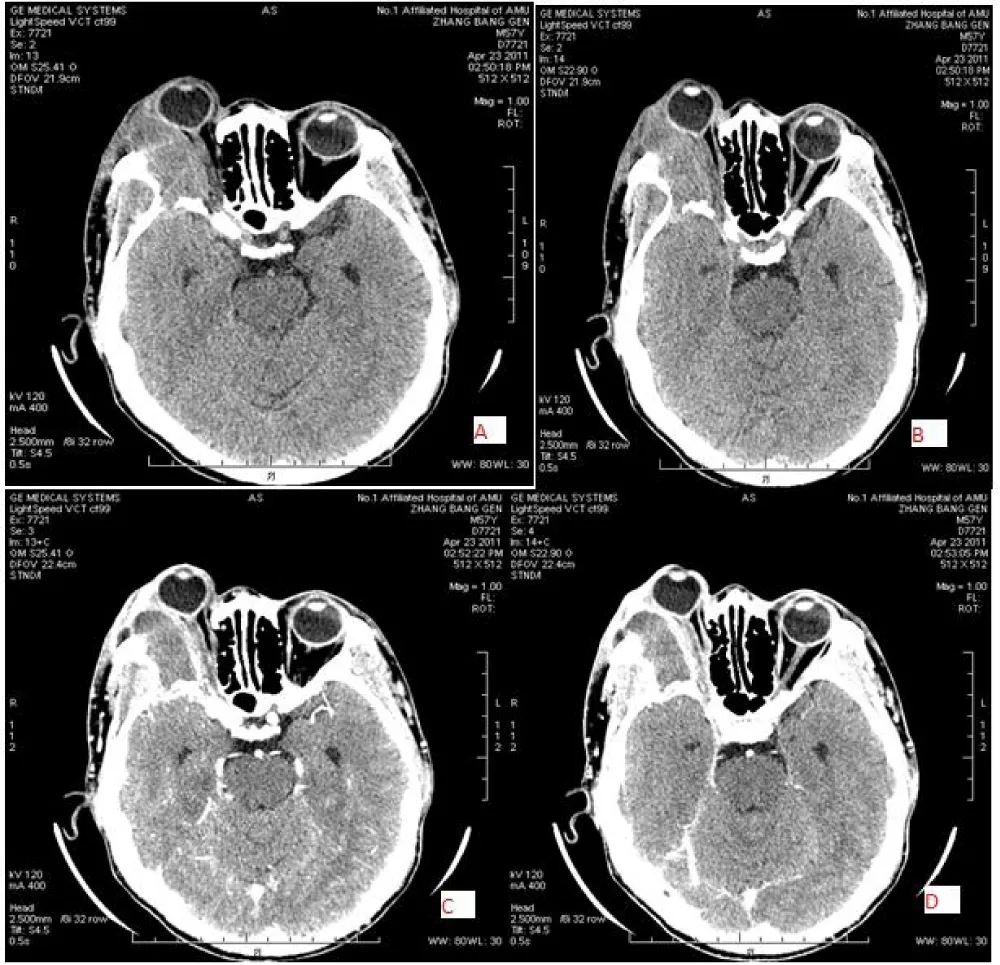

The extraconal space is located between the outside of the extraocular muscles and the inside of the orbital periosteum. In this space, mostly inflammatory and infectious diseases are seen. The inflammatory tumors include Graves’ disease, pseudotumor, granulomatous inflammation, and infectious diseases such as cellulitis and sinusitis. Orbital inflammatory pseudotumor is an idiopathic, benign, non-infectious inflammatory tumor in the orbit, with unknown causative factors. It presents with common signs and symptoms of a painful and unilateral mass, helping to distinguish it from thyroid-associated ophthalmopathy. It is usually a diffuse type of inflammatory disease and can be challenging to differentiate from other inflammatory diseases and neoplasms. However, a quick response to a trial of steroid therapy may aid in the diagnosis. Orbital lymphoma can be challenging to distinguish from orbital pseudotumor. Lymphoma is typically seen as decreased density on delayed images in dual-phase spiral CT contrast, while orbital pseudotumor is mostly seen as increased density on delayed images in dual-phase CT contrast [21]. Orbital lymphoma typically shows a brighter DWI signal and lower apparent diffusion coefficient (ADC) than normal orbital structures, whereas orbital pseudotumor shows intermediate DWI and ADC signal similar to the normal lacrimal gland [22]. Other tumors that can be found in this area include pleomorphic adenoma, adenoid cystic carcinoma, non- Hodgkin’s lymphoma, metastasis, and abscess (Figures 5-7).

Figure 6: 57-year-old male with right-sided lymphoma, located in the extraconal and superolateral region with an irregular mass and ill-defined with invaded bone, iso density (38 HU) [A&B} and slightly homogeneous enhancement(C&D).